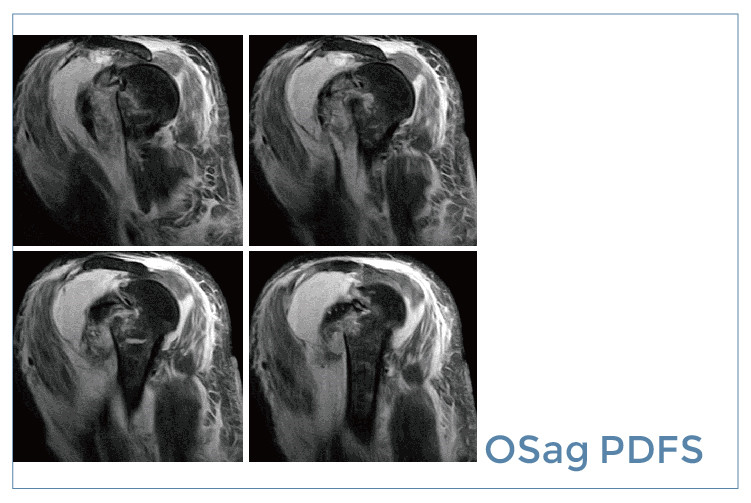

【朗润影像档案】磁共振影像病例分享(编号20190830)